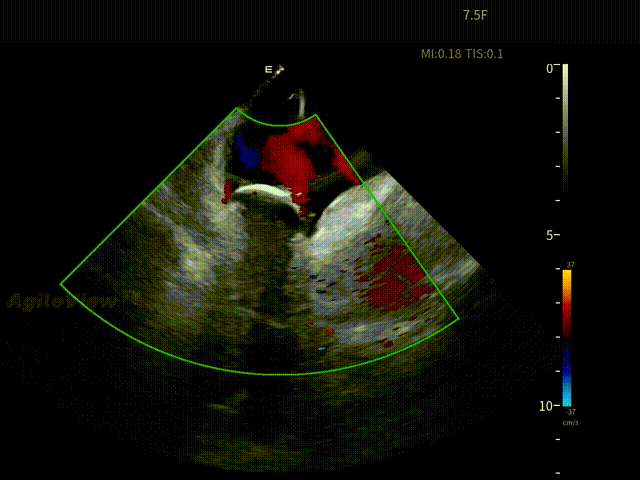

术中,基于AgileView™ 7.5Fr全球最细直径ICE导管的产品优势,周纬教授选择将ICE送入左房,以便更好地进行冷冻球囊的贴靠与位置的判断,在AgileView™ ICE实时影像的指导下, Arctic Front Advance Pro冷冻球囊导管消融导管安全进入左心房,先后完成双侧肺静脉隔离及顶部线隔离, ICE下可见导管贴靠良好,整个消融过程顺利,消融时间仅约25分钟,得益于超声设备清晰的成像质量,在顶部线隔离的时候可借助多普勒模式清晰的观察到球囊与组织的贴靠程度。 整个手术流程在ICE影像的指引下顺利完成,术中患者耐受良好,生命体征保持平稳。

盐水判断封堵效果——有少量泄露

调整后无泄漏